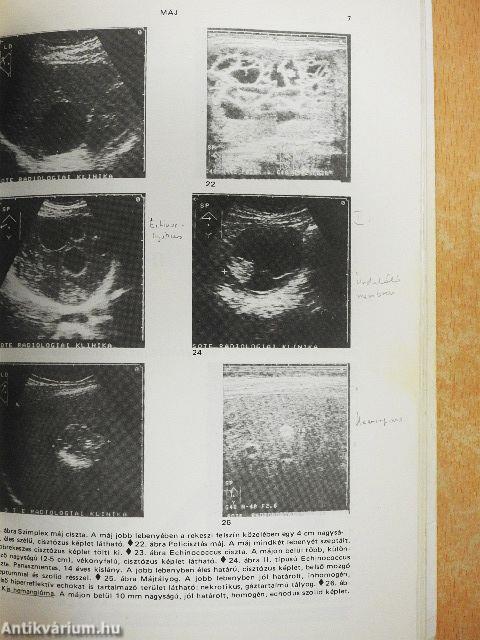

Máj55